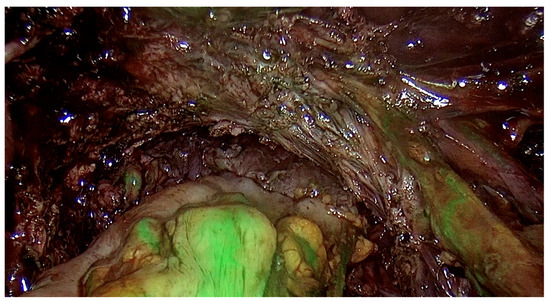

2.5. Surgery

- Improves diagnostic efficiency as the surgeon performing the examination learns to analyze ultrasound images more effectively, which can be compared with images of endometrial changes during surgery. This correlation contributes to better assessment in subsequent examinations;